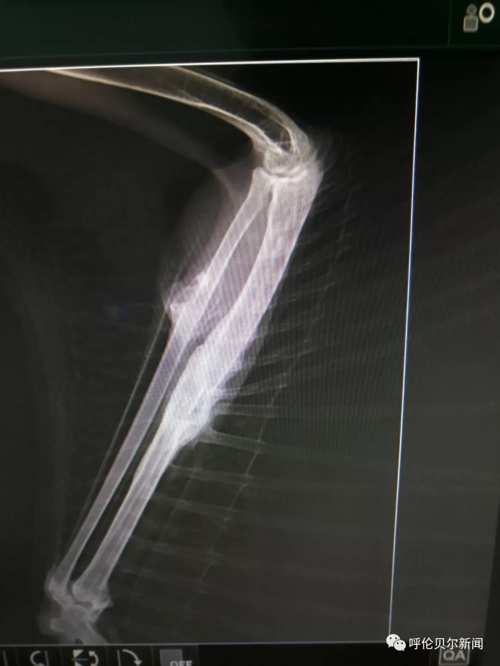

“我折了,希望有好心人能救助我!”2018年8月25日中午13:54分,双龙发了第一条关于这只雕鸮的微信朋友圈。“医院给雕鸮拍了x光片,发现右尺骨和桡骨两处骨折。身边没有能给宠物做手术的医生,我把图片发到朋友圈求助,咨询我市多名专家,他们都说桡骨非常细而且骨头很脆很难固定,手术难度太大。”双龙说。 “伤口感染,羽毛上的血渍结成了块,鸟的眼神里满是警惕和无奈,草原猛禽的风姿不再,可怜巴巴的样子,很让人心疼。”一直跟踪采访的新右旗融媒体中心记者巴图毕力格说。 >>>2018年8月31日 一边精心喂养,一边筹集为雕鸮治疗的资金,并通过微信群等方式寻找医生。经一名台湾野生保护志愿者联系,8月31日,双龙联系了毕业 于中国农业大学动物医学院、中国执业兽医师张拥军医生。 “我是一只国家二级保护动物雕鸮,我受了很重的伤,幸运的是我遇到双龙老师和张医生,他们没有放弃我……”一段雕鸮自述在腾讯公益被转载,很多野生动物保护志愿者解囊相助。5232.46元的爱心款向巴尔虎草原汇集。

在北京的张拥军医生看了X光片后表示可以进行手术,但是现在跨省运输国家二级野生保护动物审批手续繁琐时间太长,为了能够尽快手术,张拥军医生决定在海拉尔“出诊”。几经周折,双龙在海拉尔找到具备做手术条件的玩皮宠物医院,这家医院不仅同意免费提供手术场还表示愿意提供各种手术器具和药品。

>>>2018年9月3日 9月的草原日渐苍凉。清晨,双龙带着雕鸮行程300多公里来到海拉尔。一场秋雨让海拉尔这座城市清新怡人。玩皮宠物医院手术室内,来自北京的张拥军医生为雕鸮做了手术,海区几家宠物医院的医师均前来做助理、观摩学习。“手术难度比较大,术后休养也很重要,我会尽全力完成的。”张拥军医生结合20多年的临床经验,为在场的技术人员讲解手术要领。手术期间,记者进入手术室,看到双龙一边给张医生做助手,一边用蒙语安抚雕鸮。